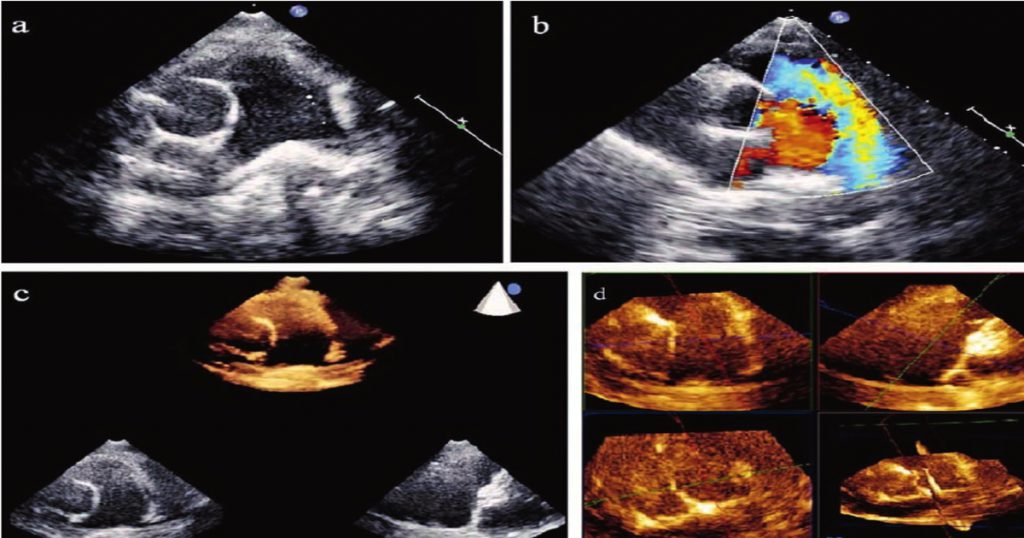

[A12295555]実践3D心エコー図法

実践3D心エコー図法【電子版】 | 医書.jp,さまざまな種類の心エコー検査「3D心エコー検査」 | VIEW Medical Gallery Site,3D心エコー:どうやって使えば手術に役立てられるか? 解剖学的評価を中心に,次世代のリアルタイム3D心エコー装置の開発-技術解説 - GEヘルスケア・ジャパン株式会社 - inNavi Suite,ACUSON SC2000」によるリアルタイムFull Volume Imagingの活用法 - 技術解説 - シーメンス・ジャパン株式会社 - inNavi Suite